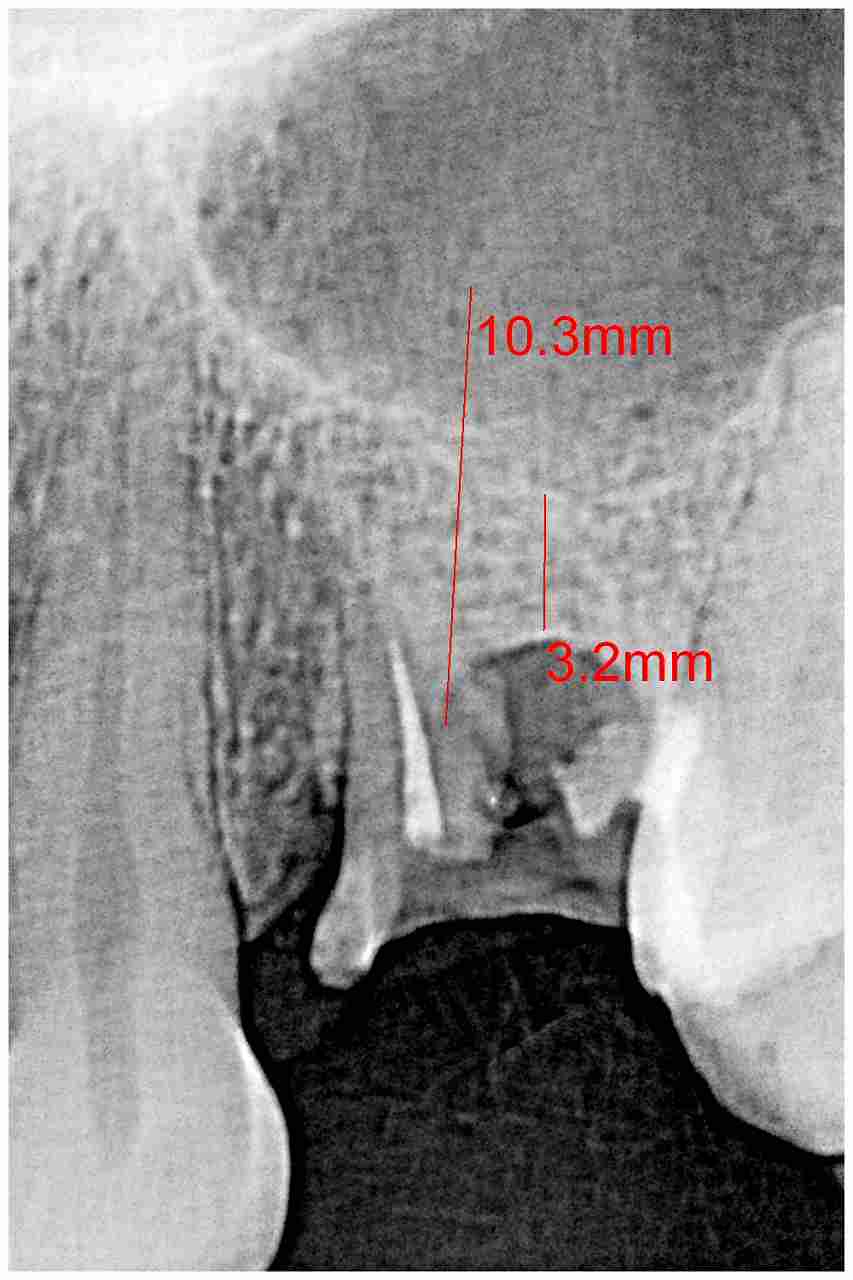

左上4番 乳歯抜歯からのインプラント埋入 審美的に仕上げる|お知らせ |広島市安佐南区の歯科医院 左上4番 乳歯抜歯からのインプラント埋入 審美的に仕上げる トップ お知らせ・ブログ お知らせ 左上4番 乳歯抜歯からのインプラント埋入 審美的に仕上げる 左上4番 乳歯抜歯からのインプラント埋入 審美的に仕上げる 4番の歯が萌出せずに、乳歯で持たせてきましたが40歳になりいよいよ被せも脱離。 抜歯の必要性があり デンタルレントゲンにても保存不可能と判断します 術前パントモになります 抜歯即時埋入時になります 埋入時のパントモになります 2か月後におなります 歯肉形態もこのようですが審美的に仕上げていきます 土台を立てて歯肉形態を仕上げていきます Web診療予約 初めての方へ 選ばれ続ける理由 院内設備について 歯が痛いしみる一般歯科 歯がぐらぐらする歯周病 健康な歯を保ちたい予防歯科 子供の虫歯予防をしたい小児歯科 銀歯をセラミックに審美歯科 白い歯を目指しませんか?ホワイトニング 矯正専門医がいるので安心矯正歯科 抜けた歯を補いたいインプラント・入れ歯 医院案内 スタッフ紹介 メリィハウス歯科クリニックオフィシャルホームページ ラベンダー歯科クリニックオフィシャルホームページ お知らせ・ブログ ホーム 診療科目 一般歯科 歯周病治療 予防治療 小児歯科 審美治療 ホワイトニング 矯正歯科 入れ歯・インプラント マウスピース矯正 初めての方へ 院長・スタッフ 設備紹介 医院案内・アクセス メニューを閉じる